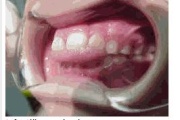

Koonilise kujuga lisahammas ülemiste tsentraalsete lõikehammaste vahel.

Suulaepoolt lõikunud koonilise kujuga lisahammas